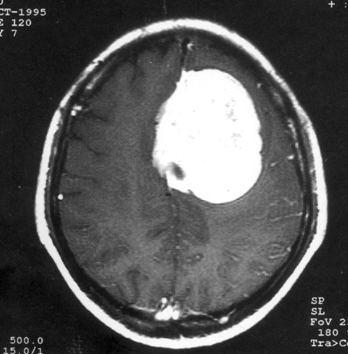

问题 病历摘要:??患者女性,37岁。大便时突起炸裂样头痛3小时,伴喷射样呕吐。既往体健。体检:T37.5℃,BP145/90mmHg,R20次/分,P85次/分。神志清楚,颅神经检查无异常,颈强直,克、布氏征(-),四肢肌力、肌张力正常,病理征(-)。 按Hunt&?Hess的动脉瘤危险性分级,该患者可分为几级?